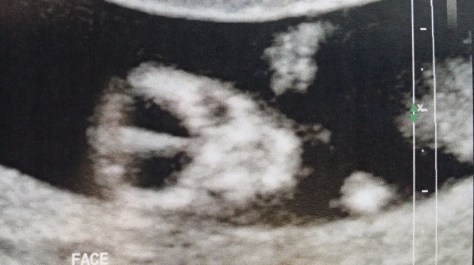

A picture of the little alien is below. It looks like an image you’d see in the credit sequence of ‘The X Files’. I imagine if Scully and Mulder finally had a baby it would look like this!